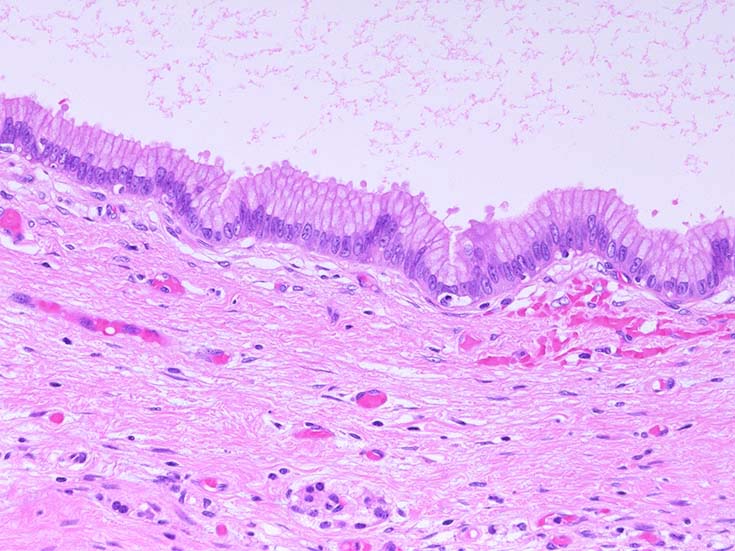

膵上皮内腫瘍性病変 pancreatic intraductal neoplasm(PanIN)*16

Low-grade PanINとhigh-grade PanINの分類

low-grade PanIN

high-grade PanIN

PanINの図譜はJohns Hopkins The Sol Goldman Pancreatic Cancer Research CenterのHome page*19から引用.

1. PanIN-1; PanIN発生の初期段階. 組織学的に, 核異型を伴わない, 核の極性が保たれている.

• telomereの短縮

• KRAS変異

• p16/CDKN2A変異

• Mucin(MUC)発現

2. PanIN-2, PanIN-3;

• TP53の不活化--PanINでのIHCでは機能喪失が,PanIN3のみで観察される. 膵癌発がん過程の遅い段階に出現する事象.

浸潤性膵癌では, 50-75%で不活化.

• SMAD4の不活化--PanIN3の30%で発現陰性化. PanIN-1,2では, SMAD4免疫染色は陽性. 発現の陰性化は後期PanINで発現する重要な異常*20.

浸潤性膵管癌では, 55%で不活化.

• BRCA2(DNA修復に重要な遺伝子)の不活化--PanINではPanIN3に特異的なイベント. germ line変異は浸潤性膵管癌の7~10%に認められる.

• cyclinD1過剰発現--PanIN1ではまれ, PanIN-2では29%, PanIN-3では57%と膵癌発がん過程に伴って頻度が上昇する遺伝子変化.

• COX-2の過剰発現--悪性腫瘍では, 細胞増殖, 生存, 浸潤および, 血管新生に関与. 正常膵管,PanIN-1では発現が低く, PanIN2から過剰発現頻度が高くなる.